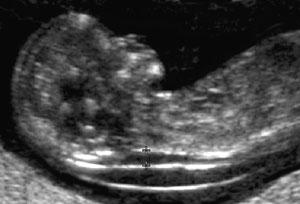

@lessiie to na prvom obrazku - tu bublinku za zatylkom a chrbatikom - to si myslela ze je NT? ...ale to vibec nie je NT, to je proste len blana, v ktorej je babo obalene😊 To NT je aj na prvej foto uplne ok😊 Mna takto vystrasili tiez, presne takto isto som to mala aj ja, hned mi teda spravil kontrolne sono na kvalitnejsim ultrazvuku a skonstatoval, ze to je len blana, ale na menej kvslitnom uzv to moze vyzerat ako NT a potom vznikaju zbytocne stresy...😊

@xarona verim ze to bude v poriadku😊 ...popravde, z tvojho obrazku si netrufam povedat, ci to je len blana ci NT, matie ma to, ze je tam ten "kopcek", ale kludne to moze byt aj ta blana😊

Tu su 2 obrazky z netu - na oboch vidno aj tu blanu aj NT...niektori dr vsak mylne povazuju za NT prave tu blanu...verim ze to bude aj tvoj pripad😊